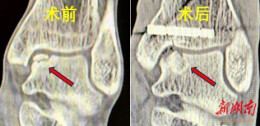

江永:骨科成功实施首例AUSS微创手术,高龄重度腰椎管狭窄患者术后三天重获行走能力